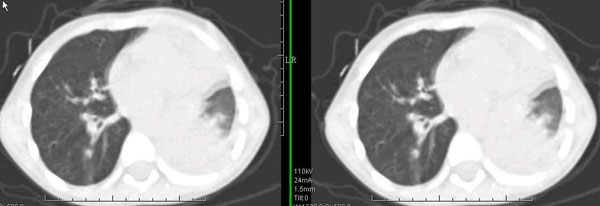

男孩,4岁,发热咳嗽4天。

下面补充ct图片:

此病人是我接手的,发热、咳嗽来做胸透,透视见左侧肺野大部密实,纵隔、心影明显左移,呼吸示纵隔摆动、膈肌矛盾运动(透视下采集了几幅图片),左肺动度明显减弱。询问病人家长,没有吃花生米等呛咳史。由于其影像特征明显,当时诊断:考虑左侧支气管异物并阻塞性肺不张、肺炎。

病人去上级医院支气管镜取出了异物。今天询问上级医院耳鼻喉科主任(是我同学),得知病人异物为胶冻样合并有少许白色粉末,后小儿说晚上喝药片时呛咳过,考虑当时为药片阻塞;另外支气管镜检发现小儿左侧支气管发育略窄,经住院抗炎治疗,现病人基本康复。

多谢各位关注及精彩点评!追踪病人结果时才知道还做过ct检查!对不起!有点晚了,刚刚下载,上传供大家参考!